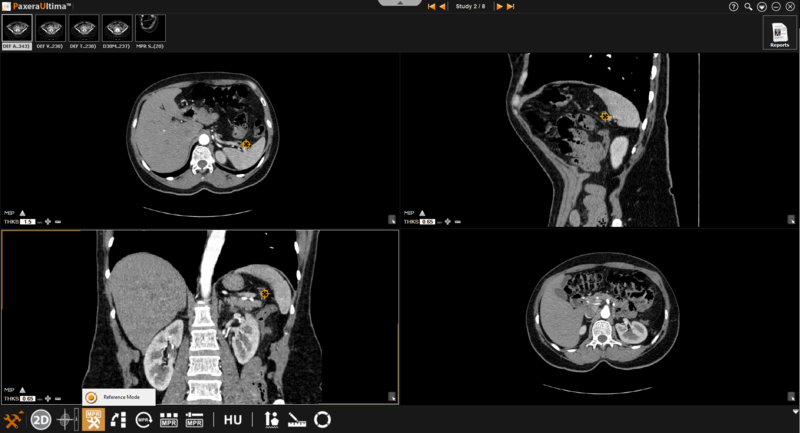

Reference mode

The reference mode is used when the user needs to refer to a specific point (rather than a specific plane). This tool is only accessible from normal & oblique mode

Follow the instructions below to change the image view to 'Reference Mode':

Click on the 'MPR Settings' button from the toolbox panel at the bottom of the screen.

Select the 'Reference Mode' button from the menu.

The lines shown on the image windows will disappear and be replaced with a point on each window.

Click and move the point to see the common coordinate (position) in all views.